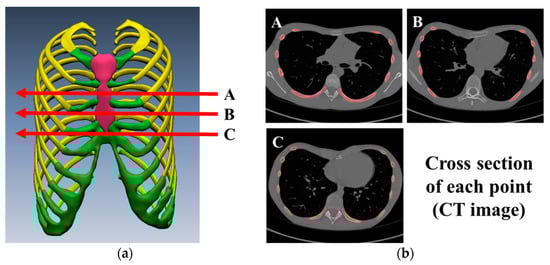

| Point | A (mm): Pre-Op. | A’ (mm): Post-Op. | B (mm): Pre-Op. | C (mm): Post-Op. | HI: Pre-Op. | ICI: Post-Op. |

|---|---|---|---|---|---|---|

| A | 217.86 | 206.97 | 73.01 | 101.11 | 2.98 | 2.05 |

| B | 215.22 | 204.46 | 68.61 | 103.49 | 3.14 | 1.98 |

| C | 217.57 | 206.70 | 73.30 | 104.15 | 2.97 | 1.98 |